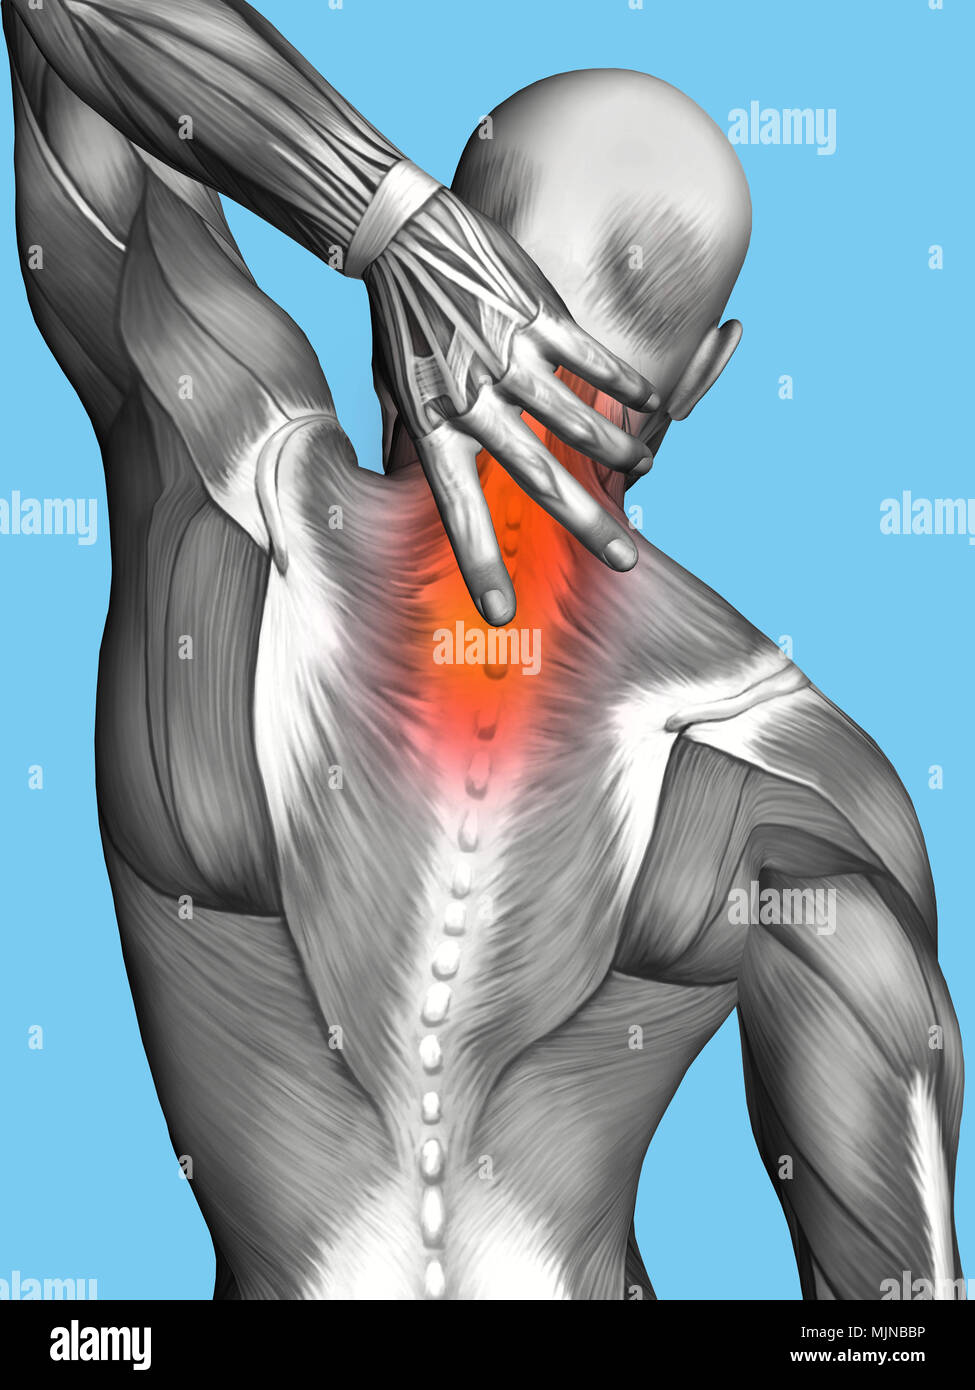

RMFX60TP–Menschen, Anatomie, Muskel, Körper, medizinische, Medizin, Illustration, Mann, Männlich, Gesundheit, muskulös, Wissenschaft, System, Biologie, Muskeln, ich

RFWW2C3P–Die männliche Anatomie, 3/4 Abbildung Muskel- und Skeletterkrankungen Systeme, Rückansicht auf schwarzen Hintergrund. 3D-Anatomie Illustration.

RFWW2BT5–Die männliche Anatomie, 3/4 Abbildung Muskel- und Skeletterkrankungen Systeme, Rückansicht auf weißem Hintergrund. 3D-Anatomie Illustration.